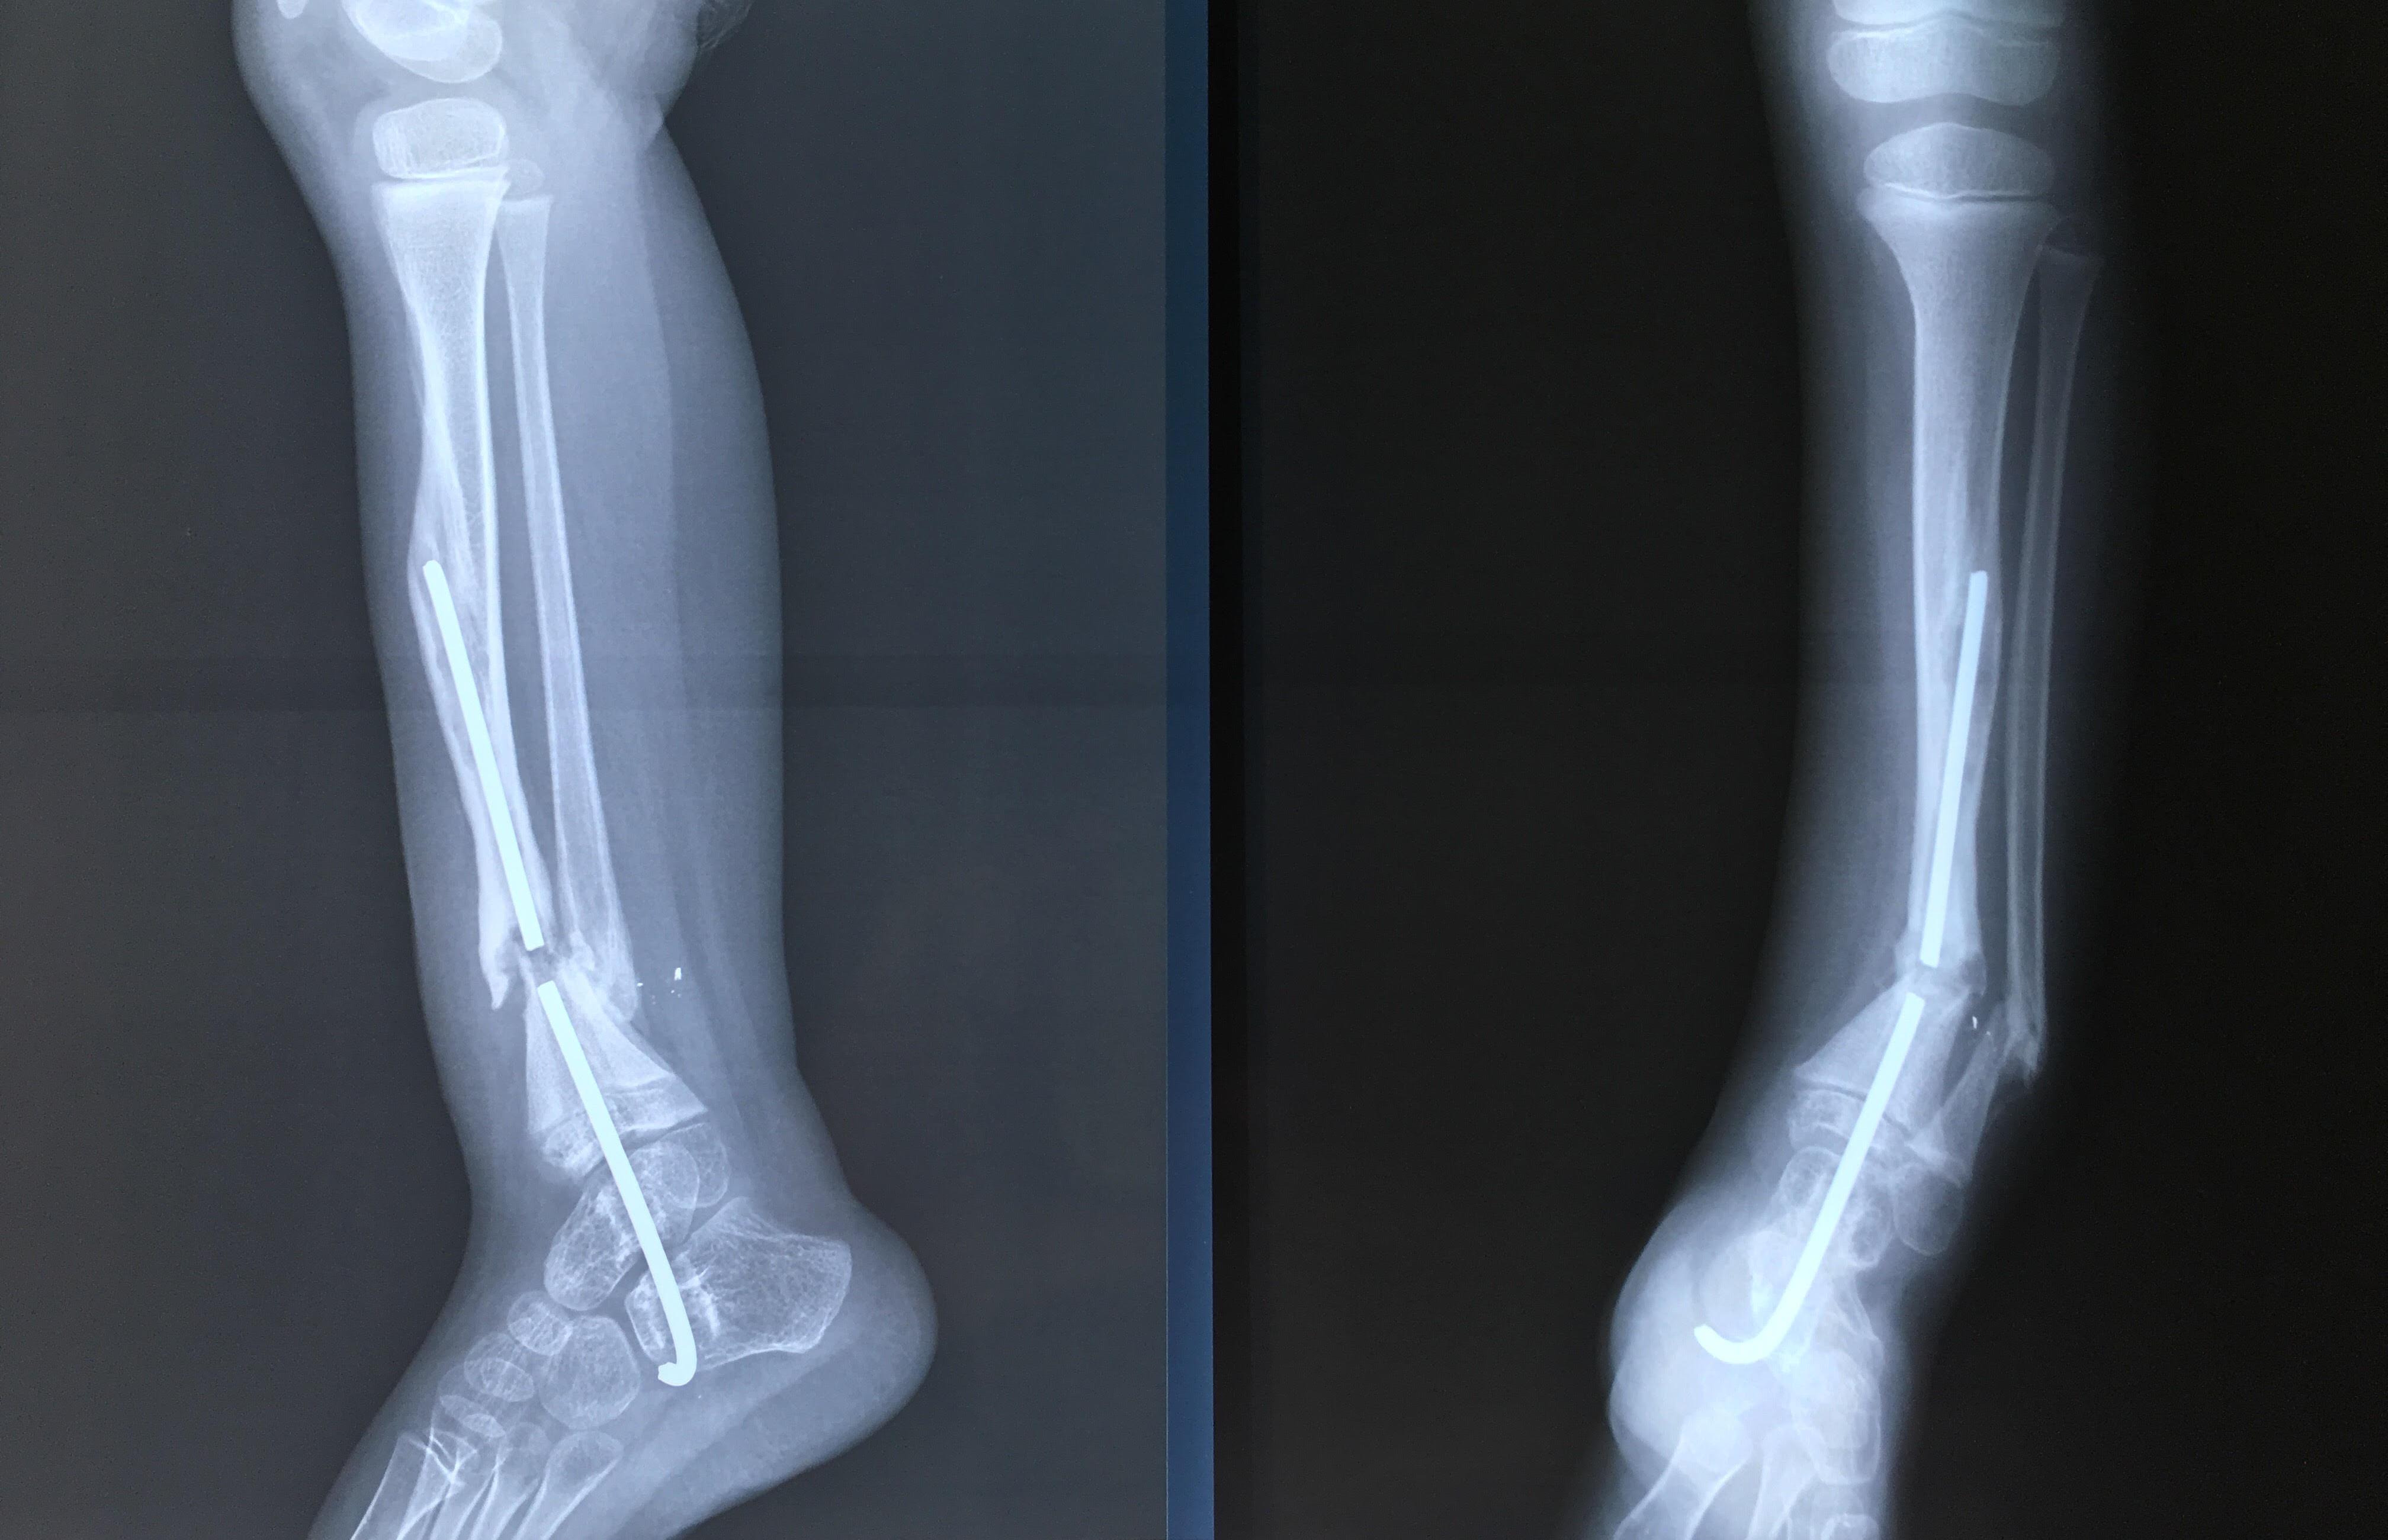

Phẫu thuật thành công ca bệnh hiếm gặp...khớp giả bẩm sinh xương chày

26/06/2019 17:00

Đã xem: 3454

Bệnh viện Chấn thương- Chỉnh hình Nghệ An, vừa phẫu thuật thành công cho bệnh nhi khớp giả bẩm sinh xương chày